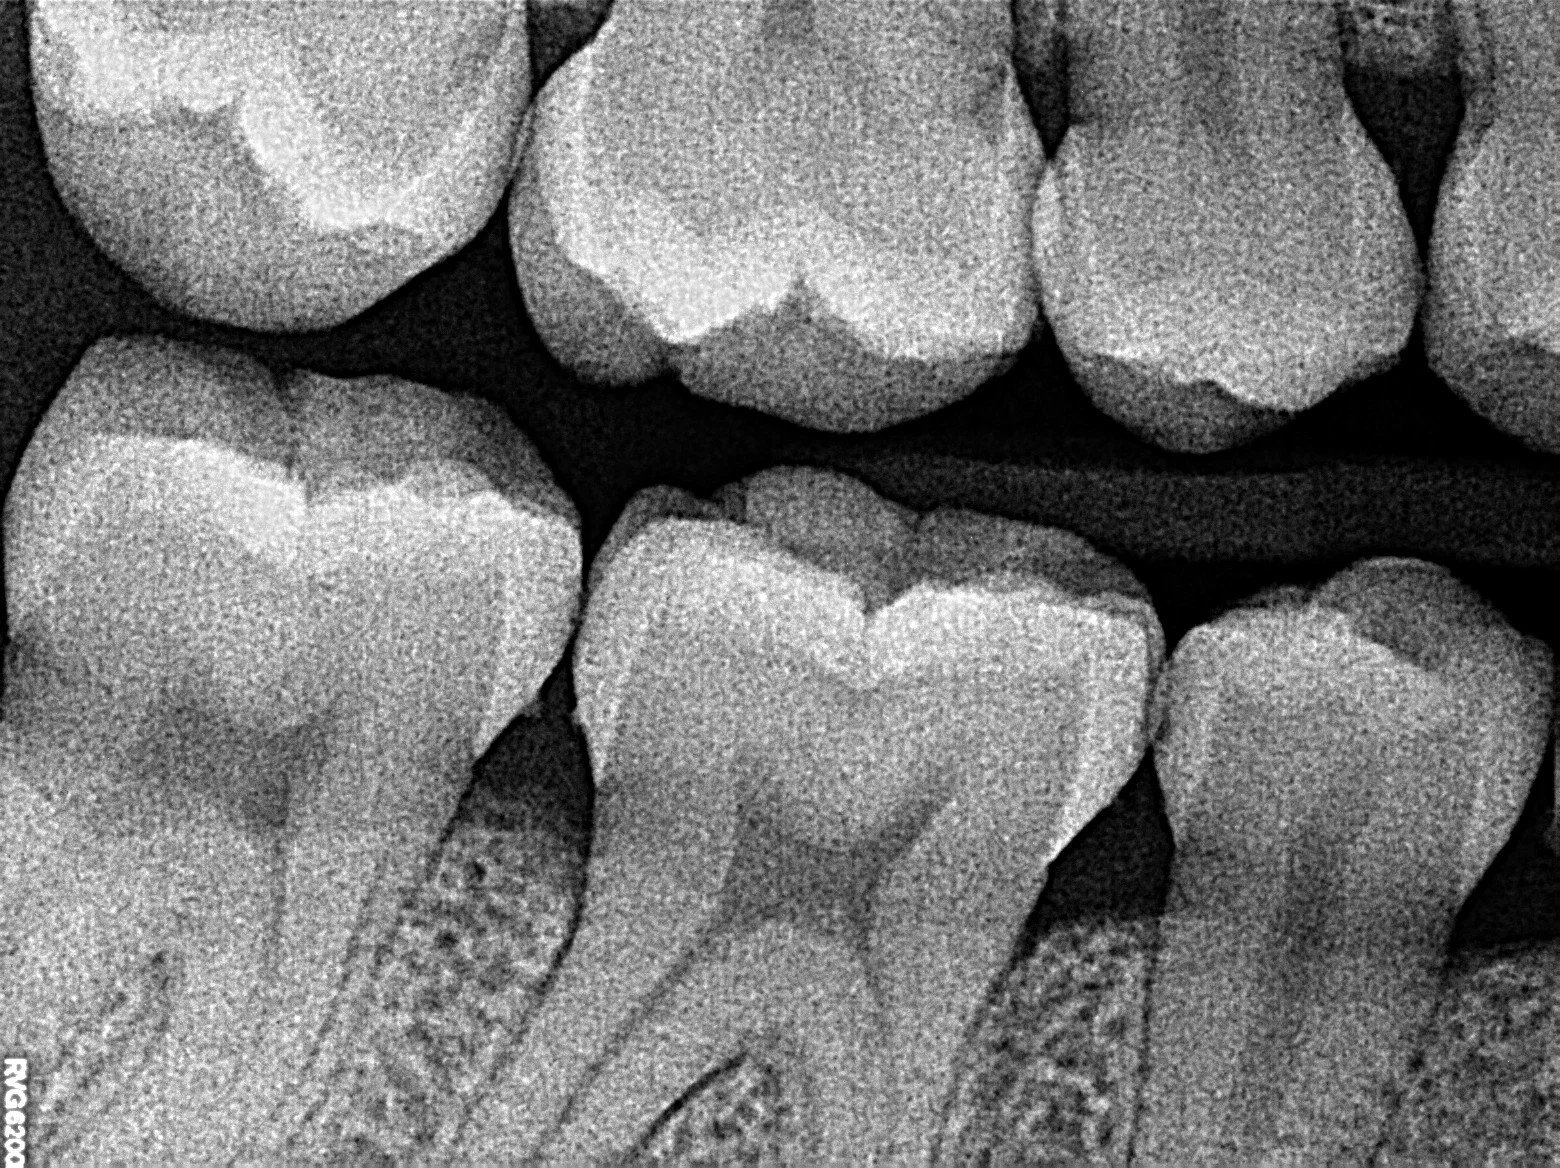

Broken or Cracked Tooth?

Unable to Eat or Chew?

Infected Wisdom Tooth?